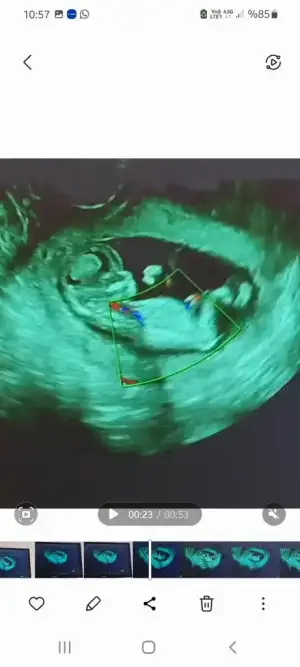

Insallah canim inşallah darısı bekleyenlerin başınaOy maşallaah ense kalınlıgı güzel testin sonucuda güzel gelecek inşallahkız bebişlerimiz çoğalıyor aynen bu sene kız senesi

Evett birde aklıma ne geldi kız dendi ama belirtilerimiz farklı farklı onlarda fos çıktı herhalde